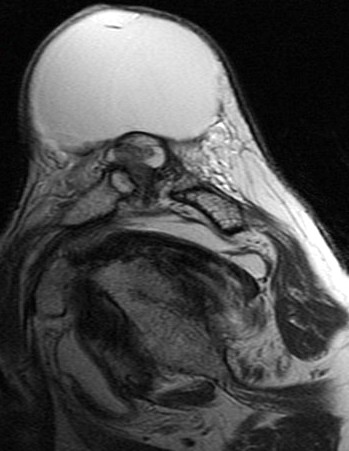

74 y/o female with mass on shoulder. Also pain. Evaluate mass and r/o rotator cuff tear.

Large cyst associated with a rotator cuff tear and AC arthrosis. Geyser phenomenon if communication shown at arthrography (some definitions specify arthrography). This was not an arthrogram. Patient also has a chronic rotator cuff tear. Reference article.

Large cyst above a degenerated acromioclavicular joint ( RID1895 )